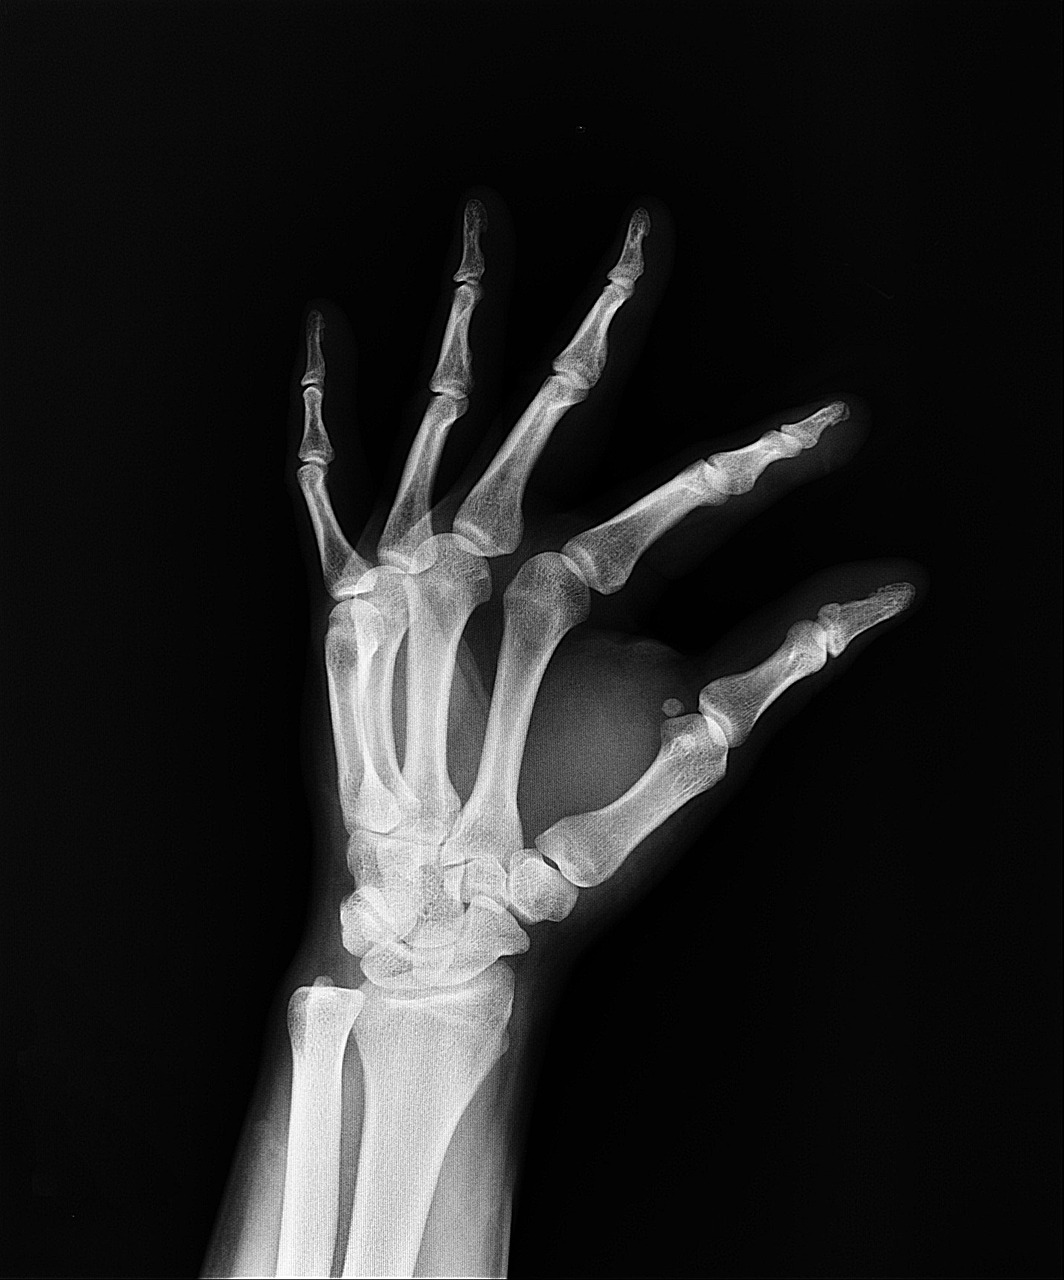

ACL断裂は、前十字靭帯が完全に切れてしまう状態を指します。この靭帯は、膝関節の安定性を保つ重要な役割を果たしており、特にサッカーなどのスポーツでは、その機能が非常に重要です。